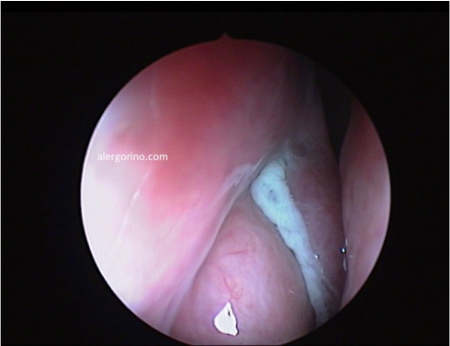

El diagnóstico se realiza mediante la historia clínica y una endoscopia nasal que proporcionan datos como la presencia de pólipos, la descarga mucopurulenta y el edema o la obstrucción de las áreas de drenaje de los senos paranasales. Si no se produjera una respuesta al tratamiento médico se evalua la situación de los senos paranasales mediante una tomografía computarizada (TC).